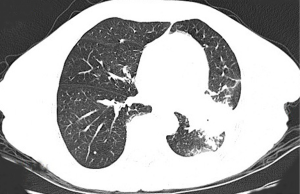

A 47-year-old, non-smoking female was referred to our hospital in January 2018 with a 1-month history of cough and phlegm. A chest computed tomography (CT) scan revealed a 5.0 cm mass in the left lower lung associated with multiple nodules in both lungs (Figure 1). Tumor biopsy pathology conducted on January 31, 2016, revealed that the patient had a stage IV (cT4N3M1) adenocarcinoma. Hematoxylin and eosin (H&E) staining revealed a typical morphology for adenocarcinoma cells (Figure 2).